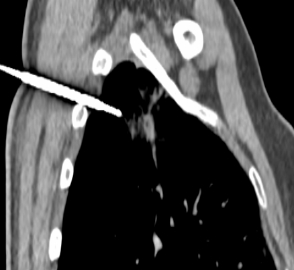

患者张女士(化名)在门诊CT检查时,发现右肺上叶占位性病变。经详细讨论并与患者及家属充分沟通后,决定实施肺结节活检穿刺术。

术前,鉴于患者病灶实性成分少,被磨玻璃成分环绕,介入放射科团队在周巍主任的带领下,通过CT精准引导,成功将一根细针经皮肤穿刺至肺结节实性部位,取出活检组织进行病理检查。整个手术过程顺利,患者术中无明显不适,术后也未出现严重并发症。术后病理结果提示为腺癌,为后续抗肿瘤治疗方案的制定提供了关键依据。